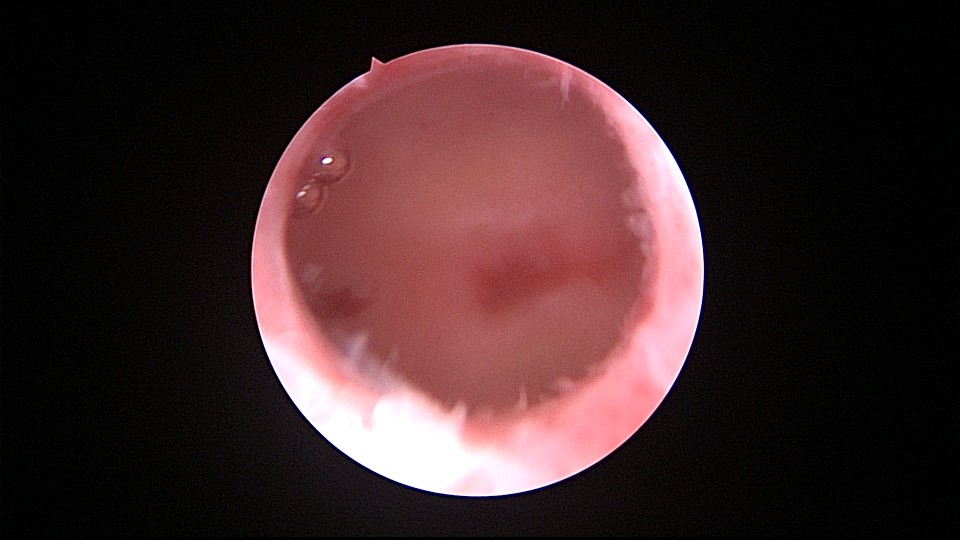

患者56岁,G2P1,剖宫产1次。安环30年,绝经7年,外院取环失败,形成假道。子宫后倾后屈位,宫颈外口萎缩狭小,宫颈管扩张膨大,宫颈管左前壁假道,宫颈内口狭窄坚硬,宫腔镜见宫腔偏向右后方,并向左后侧屈,镜子艰难进入宫腔,O型环位置正常,异物钳取出,宫腔无其他异常。